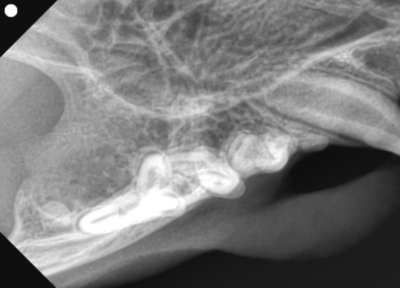

左下顎は正常な数と歯並び

左下顎は中央に重なって生えている過剰歯があります。レントゲンで確認しても、乳歯ではなく永久歯と考えられました。これらは過剰歯と呼ばれ、通常より本数が多く歯が生えてきます。かみ合わせが悪くなり、また歯間が狭くなり歯垢がつき、歯周病になりやすいです。そのため、不必要と思われる歯を抜歯しました。また、歯肉の増殖している部分を一部切り取り病理検査用の検体とし、それ以外の部分はメスで切除し正常に近い歯肉の形状に近づけました。